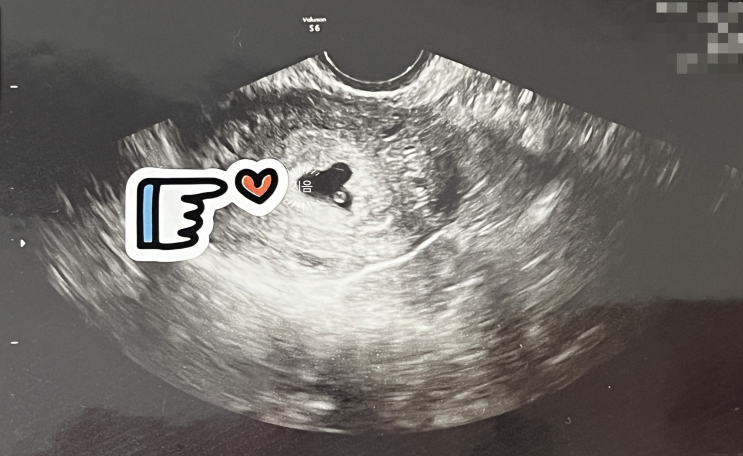

[임신일기] 8주~9주 젤리곰, 서울역차병원 졸업, 임신 축하 선물

시험관 2차 동결이식일 : 6월 7일 1차 피검 수치(+9일 차) : 717 2차 피검 수치(+11일 차) : 1,746 임신 4...

[임신일기] 6~7주 차 난황에 아기발견, 심장소리, 임신초기 출혈